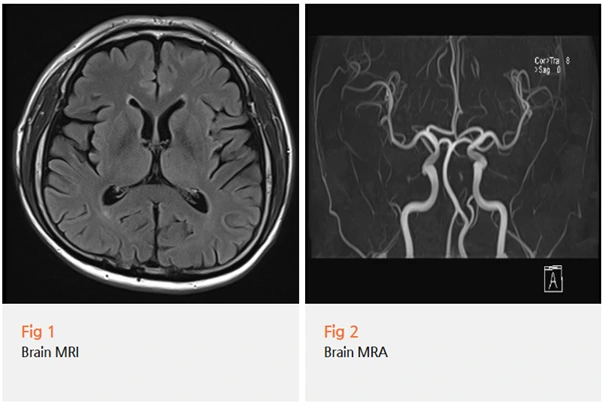

환자분께 당일 뇌 MRI와 MRA 검사를 권유드렸어요.

다행히 뇌 MRI, MRA 검사에서 뇌 안에 기질적인 이상 소견은 발견되지 않았어요.